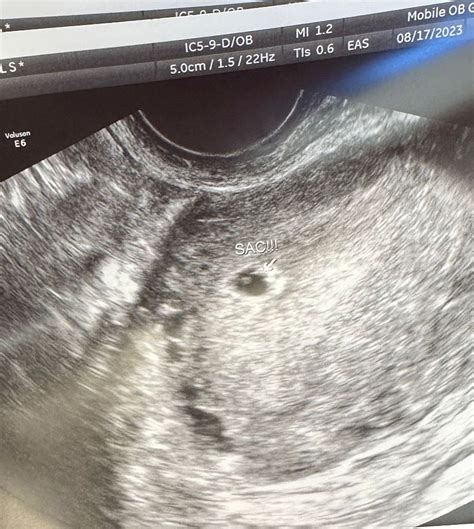

A 5 week sonogram is an ultrasound performed around the fifth week of pregnancy. At this stage, the embryo is still very small, typically measuring about 2-3 millimeters in length. The primary goal of this ultrasound is to confirm the presence of a gestational sac within the uterus, which indicates a viable pregnancy. Additionally, it helps to determine the location of the pregnancy, ruling out ectopic pregnancies, and provides an early estimate of the due date.

• Gestational Sac: The presence of a gestational sac confirms an intrauterine pregnancy.

• Gestational Sac Without Yolk Sac: This is normal at 5 weeks, as the yolk sac may not yet be visible.

• Gestational Sac with Yolk Sac: This is a positive sign, indicating that the pregnancy is progressing normally.